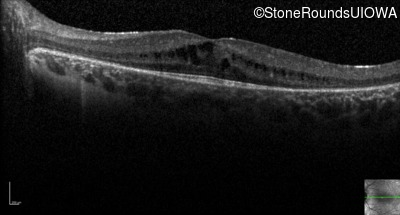

Visit at age: 19 years

Optical Coherence Tomography - Right - 20/32

Exemplar / OCT Stack

Optical Coherence Tomography - Left - 20/32